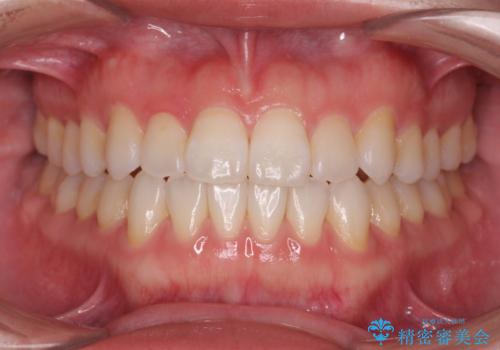

[ インビザライン ] 前歯のガタつきをマウスピース矯正で改善

![[ インビザライン ] 前歯のガタつきをマウスピース矯正で改善の症例 治療後](https://seimitsushinbi.jp/wp/wp-content/uploads/2023/06/8f8a8c7e4fc215c9167147f340f29eaf-500x350.jpg?v=1686815671)